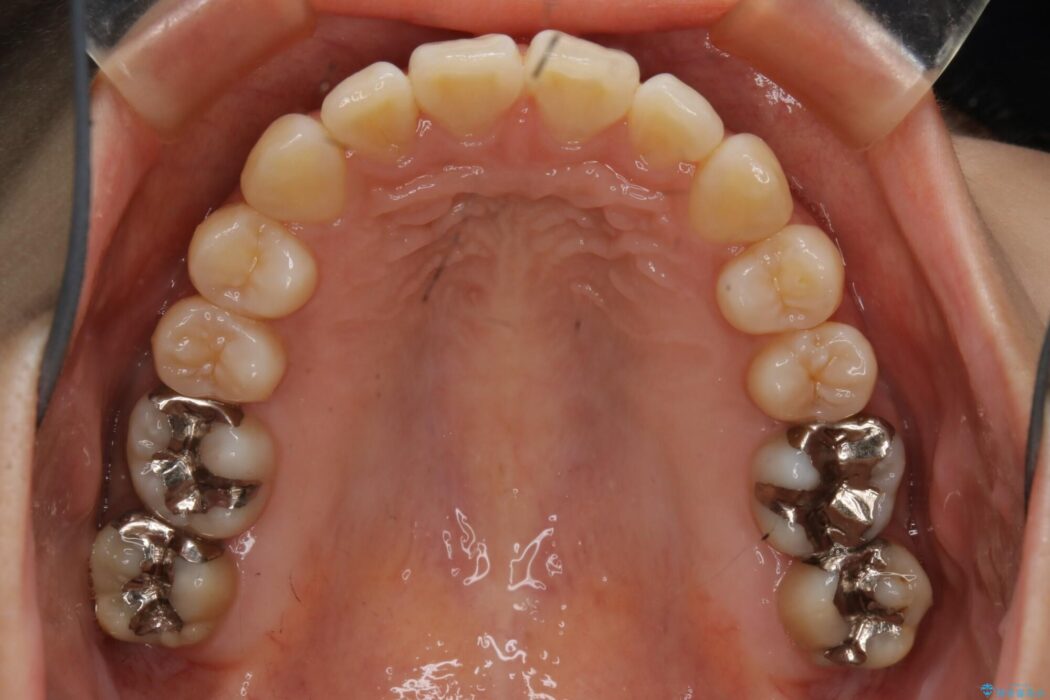

よって患者様ご希望の非抜歯かつマウスピースでの矯正を行うために、最大量の臼歯の遠心移動をして歯列全体を奥へ引っ込める計画をご提案しました。

非抜歯での矯正治療

マウスピースにマイクロインプラントという補助装置を併用することで抜歯をせずとも歯列を整えるスペースを確保することができます。奥歯から順に移動させていくので前歯に変化が出るまでには時間がかかってしまいますが、健康な歯を抜歯することなく理想的な歯並びを手に入れることができます。